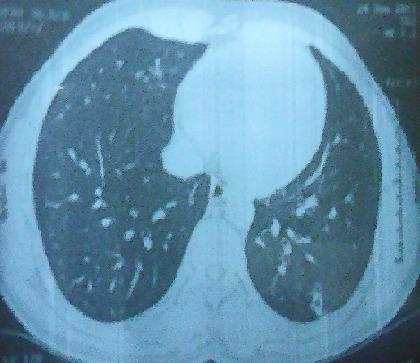

[Mediastinal primary amyloidosis of pseudo tumor appearance].

摘要